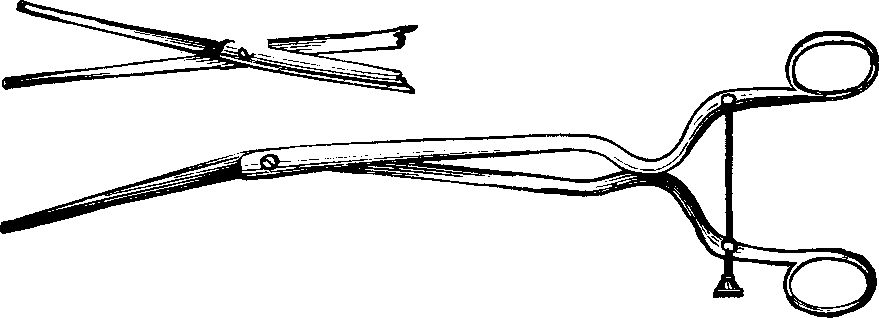

Fig. 3. THE UTERINE DILATOR. This instrument is introduced

into the canal of the uterine neck with its blades closed. By means of the

thumb-screw the blades are then separated as shown in this illustration,

the cervical canal being thereby dilated to the required extent.

Treatment. From the nature of this malady, it will readily be seen that no medical treatment can effect a radical cure. We must therefore resort to surgery. In a small proportion of cases, the stricture may be cured by repeated dilations of the constricted part of the cervical canal. This may be accomplished by using a very smooth probe which is fine at the point, but increases in size, so that its introduction will widen and expand the orifice and canal. The stricture may be overcome in many cases by using different sized probes. In some instances, we have employed the uterine dilator, represented by Fig. 3. We have also introduced sea-tangle and sponge tents into the neck of the womb, and allowed them to remain until they expanded by absorbing moisture from the surrounding tissues. The latter process is simple, and in many cases preferable. By means of a speculum (see Figs. 15 and 16), the mouth of the womb is brought into view, and the surgeon seizes a small tent with a pair of forceps and gently presses it into the neck of the womb, where it is left to expand and thus dilate the passage. If there seems to be a persistent disposition of the circular fibers of the cervix to contract, and thus close the canal, a surgical operation will be necessary to insure permanent relief. In performing this operation, we use a cutting instrument called the hysterotome (see Figs. 4 and 5). By the use of this instrument, the cervical canal is enlarged by an incision on either side. The operation is but slightly painful, and, in the hands of a competent surgeon, is perfectly safe. We have operated in a very large number of cases and have never known any alarming or dangerous symptoms to result. After the incision, a small roll of cotton, thoroughly saturated with glycerine, is applied to the incised parts, and a larger roll is introduced into the vagina. The second day after the operation, the cotton is removed, the edges of the wound separated by a uterine sound or probe, and a cotton tent introduced into the cervix, and allowed to remain, so that it will expand and thus open the wound to its full extent. This treatment must be thoroughly applied, and repeated every alternate day, until the incised parts are perfectly healed.